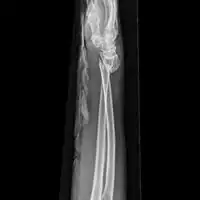

Front view of bowing fractured radius and ulna -

Side view of bowing fractured radius and ulna